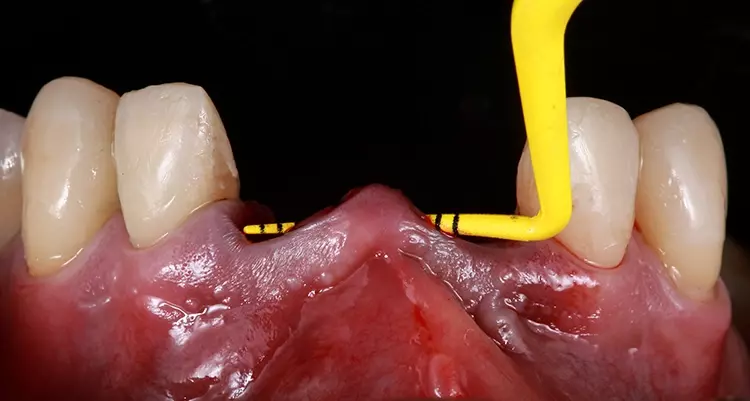

Das Trauma an den oberen mittleren Schneidezähnen führte zu Wurzelresorptionen und einem Mobilitätsgrad 3. Der Patient zeigte Schmerzen an bei der Perkussion von Zahn 21. Die Kronenversorgung der beiden mittleren Schneidezähne war insuffizient.

Die röntgenologischen und computertomografischen Untersuchungen zeigten, dass die Wurzeln der mittleren Schneidezähne Anzeichen von Resorption aufwiesen. Zusätzlich waren auch Aufhellungen sichtbar, was auf mögliche periapikale Granulome hindeutete.

Die Bohrschablone wurde additiv aus speziellem 3D-Druckharz (Cosmos SG, Yller) auf einem Photon Mono 4K (Anycubic) hergestellt. Die Zähne wurden atraumatisch unter Erhaltung der Integrität der Gingiva und der Gingivaarchitektur extrahiert (Abb. 11).